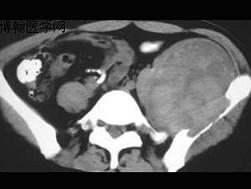

问题 患者,男性,33岁,近2年来感左髂部疼痛,活动后加重,3周前由于剧烈运动后左下肢活动不能,查体左髋压痛明显,皮肤稍显红肿,请结合所提供的图像,选择最佳选项 ( )

选项 A、软骨瘤 B、软骨肉瘤 C、骨巨细胞瘤 D、骨囊肿 E、动脉瘤样骨囊肿

答案 E